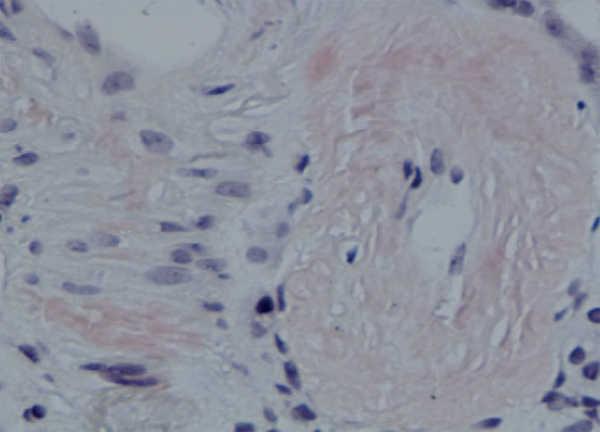

Se decidió realización de biopsia renal para filiar el diagnóstico, observándose 9 glomérulos esclerosados. Se detectaron, además, depósitos amorfos en glomérulo, vaso e intersticio, rojo Congo positivo y amiloide AA (IHQ) + en distribución glomérulo-intersticial, nodular y predominantemente perivascular. El diagnóstico anatomopatológico fue amiloidosis renal de tipo AA con afectación glomerular, intersticial y fundamentalmente vascular. (figura 2, figura 3, figura 4 y figura 5).

Figura 2. Técnica de hematoxilina-eosina en la que se observan nódulos amorfos en glomérulos y vasos.